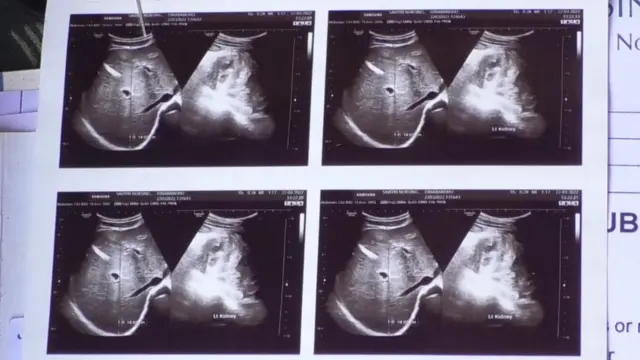

“సాధారణంగా రక్తంలో సిరం క్రియాటినిన్ 1.2 mg/dL (మిల్లీ గ్రామ్/డెసీలీటర్ - వీటిని స్థానికులు పాయింట్లు అంటారు) కంటే ఎక్కువగా ఉంటే, మూత్రపిండాలు సరిగా పని చేయడం లేదని అర్థం.

ఉద్దానం ప్రాంతంలో దాదాపు 15 వేల మందికి సీరం క్రియాటినిన్ 3 నుంచి 25 mg/dL ఉంది. 80 శాతం కంటే ఎక్కువ కిడ్నీలు పని చేయడం మానేస్తే, వారికి డయాలసిస్ అవసరమవుతుంది” అని శ్రీకాకుళానికి చెందిన నెప్రాలజిస్ట్, కిడ్నీ వ్యాధిగ్రస్థుల కోసం నిర్వహిస్తున్న సామాజిక ఆసుపత్రి వైద్యులు డాక్టర్ విద్యాసాగర్ బీబీసీకి తెలిపారు.

మరో వైపు ఇక్కడ డయాలసిస్ స్టేజ్కు వచ్చే వరకు బాధితుల్లో కిడ్నీవ్యాధి లక్షణాలు కనపడవు” అని డాక్టర్ విద్యాసాగర్ బీబీసీతో అన్నారు.